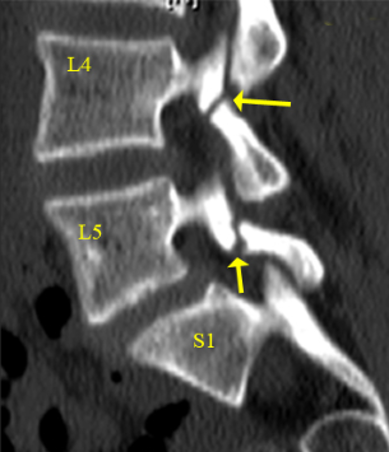

The surgeon removes the damaged disc or diseased bone, places a cage or bone graft between the vertebrae, and secures it with screws and rods. Over months, the bones heal together naturally. The surgical approach (front, back, or side) depends on the patient's specific condition and body type.

Transforaminal Lumbar Interbody Fusion – performed from the back through a small opening, allowing access to the disc space with minimal disruption to spinal structures.

Oblique Lumbar Interbody Fusion – performed from the side, avoiding major back muscles and reducing tissue damage while providing excellent disc space access.

Posterolateral Fusion – fusion at the back of the spine without removing the disc, typically used when the front of the spine is stable.

Anterior Lumbar Interbody Fusion – performed through the abdomen, placing implants in front of the spine for optimal disc space restoration.